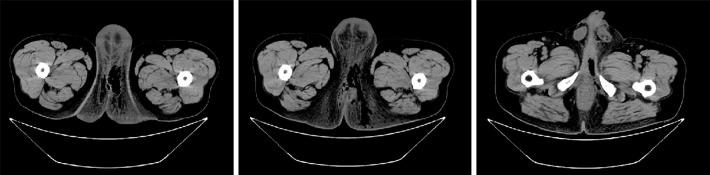

Contemporary diagnosis and management of Fournier's gangrene.

Ther Adv Urol. 2015 Aug;7(4):203-15. doi: 10.1177/1756287215584740.

Fournier's gangrene: our experience with 50 patients and analysis of factors affecting mortality.

World J Emerg Surg. 2013 Apr 1;8(1):13. doi: 10.1186/1749-7922-8-13.

Fournier's Gangrene: Current Practices.

ISRN Surg. 2012;2012:942437. doi: 10.5402/2012/942437. Epub 2012 Dec 3.